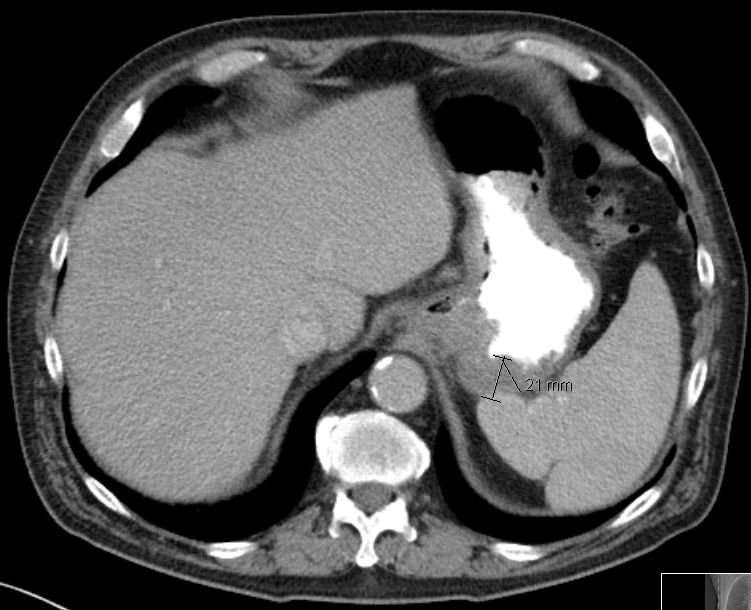

| Magenantrum | 54-jährige Frau mit obstruierendem Magenantrumkarzinom. ![]() |